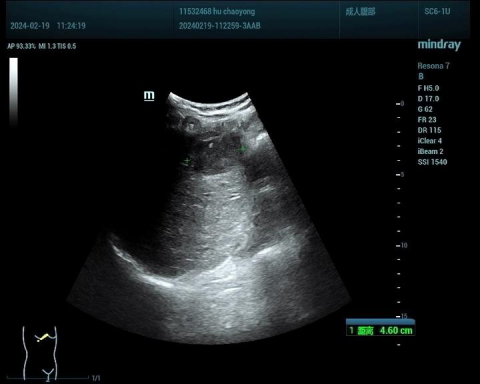

肝血管瘤